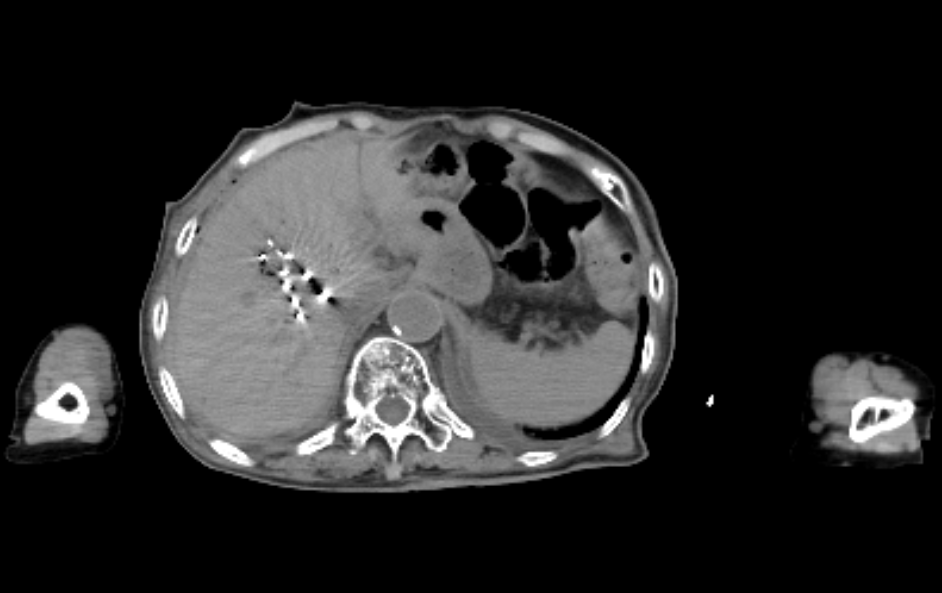

2、术中精准引导:CT实时引导下,按3D打印模板预设粒子植入穿刺针道,术中避开大血管及胆管,实时CT扫描确认18G粒子植入穿刺针尖置于肿瘤远端预定位置后,采用退针法逐步植入碘125粒子,全程可视化操作,避免了传统手术中穿刺偏差导致的粒子分布不均或误损伤正常组织的风险。

3、术后精准验证:术后通过CT扫描重建粒子分布影像,显示碘125粒子均匀分布覆盖病灶,无冷区,与术前规划方案进行剂量对比验证,确保碘125粒子分布完全符合预设要求。